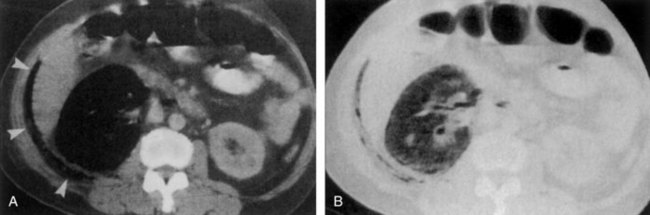

Ultrasonography and CT establish the diagnosis. On ultrasonography the lesion is typically poorly marginated and relatively sonolucent with occasional low-amplitude echoes that disrupt the cortical medullary junction (Corriere and Sandler, 1982) (Fig. 10–21A). Enhancement with a contrast agent is necessary with CT studies because the lesion is difficult to visualize on the unenhanced study (see Fig. 10–21B). Wedge-shaped areas of decreased enhancement are seen. No definite wall is evident, and frank liquefaction is absent. Conversely, abscesses tend to have liquid centers, are usually round, and are present both before and after contrast medium enhancement. More chronic abscesses may also show a ring-shaped area of increased enhancement surrounding the lesion (Corriere and Sandler, 1982). Gallium scanning reveals uptake that is in the region of and larger than the previously demonstrated mass (Rosenfield et al, 1979). In patients with multifocal disease the findings are similar but multiple lobes are involved.

Figure 10–21 Acute focal bacterial nephritis. A, Ultrasound image: longitudinal view of the left kidney demonstrates spleen (S) and left kidney (arrows). Note irregular midpole mass (M) of slightly higher echo texture than surrounding normal renal parenchyma. B, Contrast medium–enhanced CT scan demonstrates a wedge-shaped area of low density (arrows) in the middle portion of the left kidney. The findings resolved after antimicrobial therapy.

(From Schaeffer AJ. Urinary tract infections. In: Gillenwater JY et al, editors. Adult and pediatric urology. Philadelphia: Lippincott Williams & Wilkins; 2002. p. 211–72.)